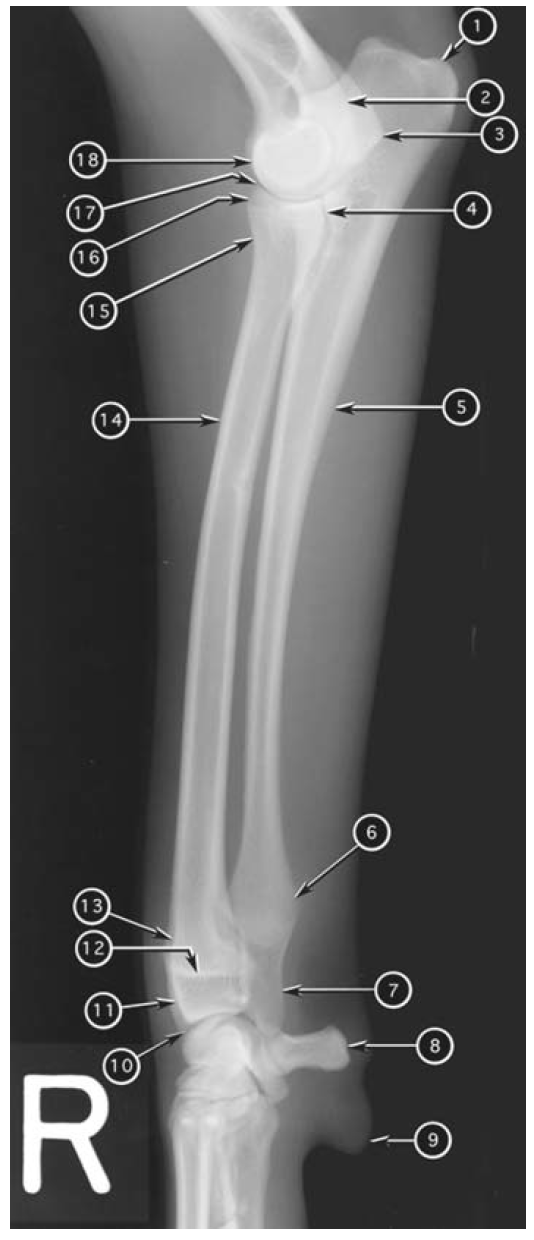

Mediolateral radiograph of canine humerus

What number?

- Greater tubercle of humerus

- Proximal physis of humerus

- Head of humerus

- Condyle of humerus

- Lateral epicondyle of humerus

- Medial epicondyle of humerus

- Anconeal process of ulna

- Lateral coronoid process of ulna

- Medial coronoid process of ulna

- Tuber olecrani

- Head of radius

- Proximal radioulnar joint

- Infraglenoid tubercle of scapula

- Supraglenoid tubercle of scapula

A

1. Infraglenoid tubercle of scapula

2. Head of humerus

3. Anconeal process of ulna

4. Lateral epicondyle of humerus

5. Tuber olecrani

6. Medial epicondyle of humerus

7. Lateral coronoid process of ulna

8. Proximal radioulnar joint

9. Medial coronoid process of ulna

10. Head of radius

11. Condyle of humerus

12. Proximal physis of humerus

13. Greater tubercle of humerus

14. Supraglenoid tubercle of scapula